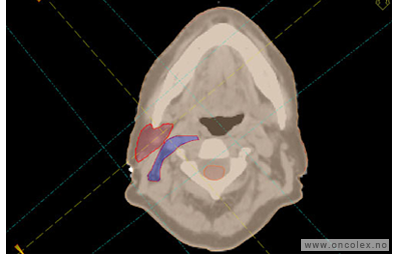

Målvolum

Skisse over hvordan strålefeltet planlegges:

Illustrasjon for målvolum

• GTV (Gross Tumor Volume): Identifisert tumor.

• CTV (Clinical Target Volume) GTV + omkringliggende vev hvor det kan væremikroskopisk spredning.

• ITV (Internal Target Volume): CTV + en indre margin som tar hensyn tilindre bevegelser og endringer av CTV.

• PTV (Planning Target Volume): Innstillingsmargin som inneholder ITV og samtidig tar hensyn til antatte pasientbevegelser, samt variasjoner i pasientopplegging og feltinnstillinger.

• Feltgrense. Tegnes som oftest på kroppen.

ICRU (International Commission on Radiation Units and Measurements)